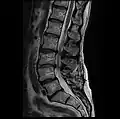

MRI lumbar spine with degeneration, post-hemilaminectomy L4-5 (sagittal FAST STIR)- MRI lumbar spine post-hemilaminectomy (sagittal T2 FRFSE)